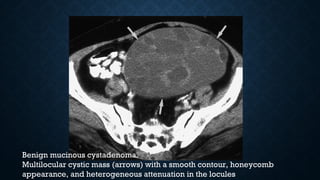

Benign mucinous cystadenoma.

Multilocular cystic mass (arrows) with a smooth contour, honeycomb

appearance, and heterogeneous attenuation in the locules

Benign mucinous cystadenoma. Multilocularcystic mass (arrows) with a smooth contour, honeycomb appearance, and heterogeneous attenuation in the locules